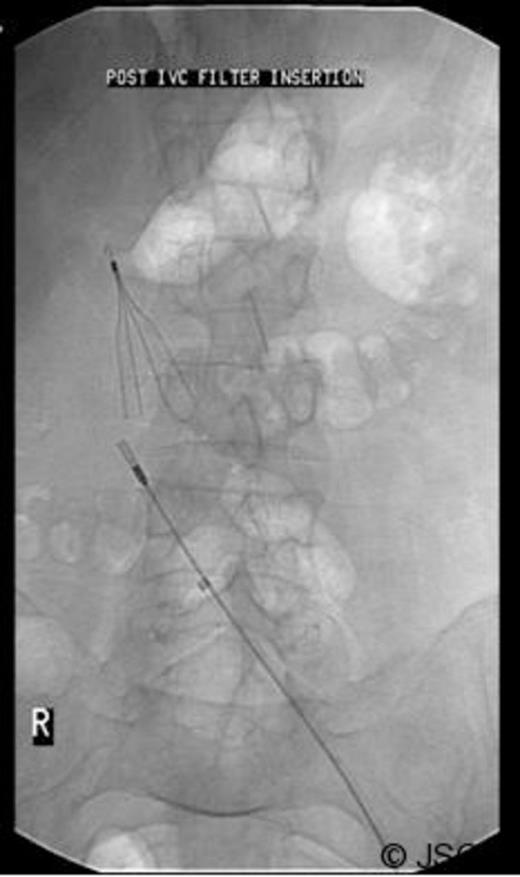

To avoid thrombus escaping from the iliac vein at the time of revision, a vena cava filter was inserted from the contralateral femoral vein (Figure 3).

Inferior vena cava (IVC) filter inserted prior to revision surgery